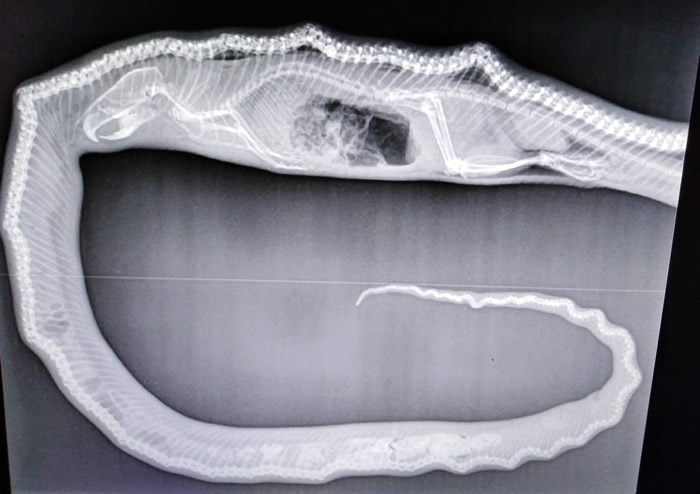

(蜘蛛网eeook.com报道)据ETtoday:澳洲达尔文(Darwin)野生动物保护组织上月29日发现一条大水蟒疑似遭车辆撞击,送医抢救后不治。特别的是, 院方透过X光片清楚拍下它的「最后的晚餐」,推测可能是它吃太饱,导致爬行速度变慢,才会在过马路时出车祸。

野生动物救援组织Wildlife Rescue Darwin在脸书分享这张照片,表示他们对无法救回水蟒感到遗憾,但透过X光片,至少可以确定它生前最后吃了一顿丰盛的晚餐。

负责治疗的副院长Andrea Ruske表示,「有趣的是,这只水蟒吃了一只大老鼠,而且连骨头也变形了。」她猜测,水蟒之所以被撞到,很可能是因为吃太饱,导致行动缓慢,因此在过马路时发生憾事。

许多网友看完感到不可思议,怀疑水蟒可能本身就有严重骨头疾病;组织粉专则回覆,「对,它同时也有代谢性骨病,这在野生蛇类中相当少见,但可以肯定的是它绝不是宠物。」